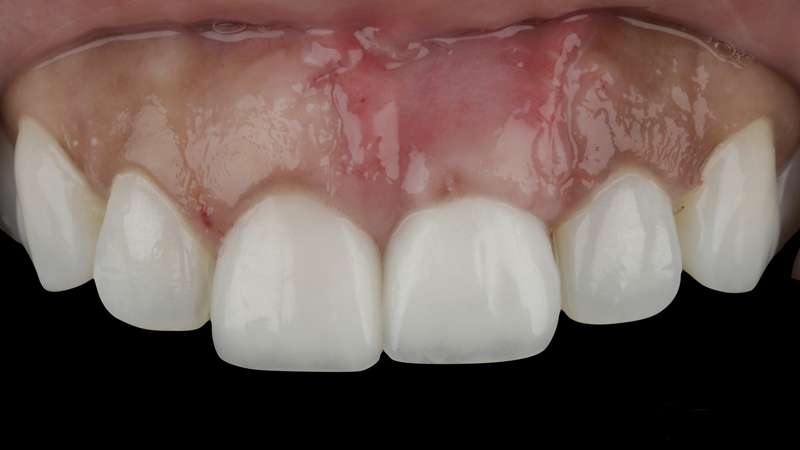

(9.) Postoperative photographs acquired after 2 weeks and 3 months of healing, respectively, demonstrating the reconstitution of an ideal tooth No. 9 marginal position in relation to its contralateral counterpart with increased soft-tissue thickness.

Figure 9

The patient in this case had undergone implant therapy at the site of tooth No. 9 and was restored with a cement-retained restoration more than 5 years prior. At presentation, the site demonstrated a peri-implant soft-tissue dehiscence that extended approximately 3-mm apical to the gingival margin of tooth No. 8. Thin and erythematous marginal tissue was evident at the zenith (Figure 2). The crown was removed, and a partial thickness flap was reflected using a papilla-sparing incision design. This revealed that the implant was positioned too far facially and that its body was visible through a very thin layer of bone (Figure 3 and Figure 4). The first objective of treatment was to minimize the facial extent of the emerging abutment and crown. To accomplish this, the facially positioned abutment and implant crown margin were both recontoured. The second treatment objective was to provide additional supracrestal soft tissue that would more adequately maintain the peri-implant margin. The tuberosity was selected as a donor site due to its dense, high-quality connective tissue, low propensity for shrinkage, and association with minimal patient discomfort. Once the graft was secured (Figure 5 through Figure 7), the flap was coronally positioned (Figure 8). After a healing period of 2 weeks, the margin of tooth No. 9 exhibited an ideal position in relation to its contralateral counterpart and demonstrated increased soft tissue thickness (Figure 9). Three months postoperatively, further healing had improved the esthetics and the position of the margin had been maintained (Figure 10).